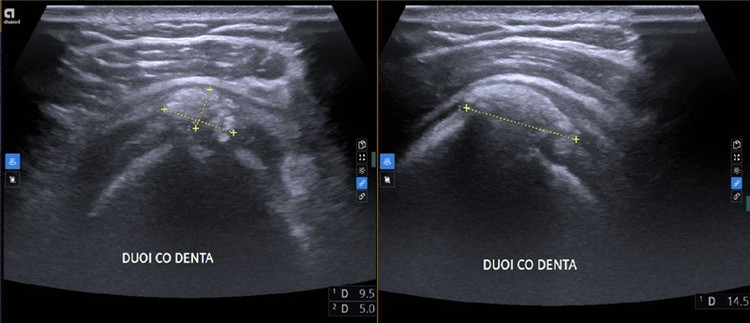

Kết quả chụp X-quang khớp vai cho hình ảnh vôi hóa cạnh mấu động lớn xương cánh tay. Siêu âm khớp vai phát hiện vôi hóa gân trên gai vai phải, kèm theo hình ảnh viêm bao hoạt dịch dưới cơ delta.

Kết quả siêu âm khớp vai của bệnh nhân phát hiện vôi hóa gân trên gai vai phải, kèm theo hình ảnh viêm bao hoạt dịch dưới cơ delta. Ảnh Medlatec